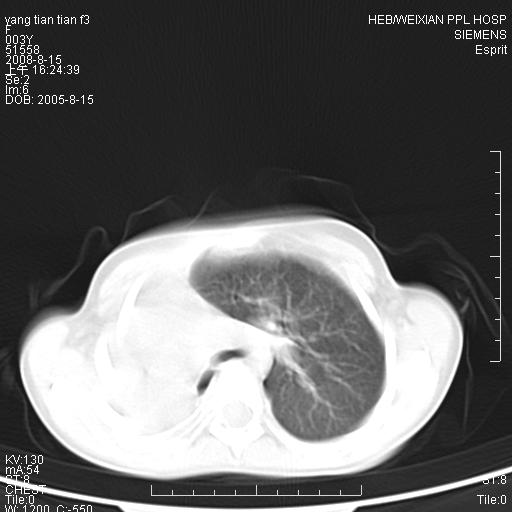

患儿,女,5岁,平素活动后气短,左侧面瘫.右侧胸廓较左侧塌陷.

两侧胸廓不甚对称,左侧稍膨隆,右肺体积明显变小,密度增高,未见正常通气肺组织,纵隔结构明显右移,心脏边缘欠清,外形似增大。纵隔血管间隙不清晰,左肺外形增大,部分肺组织突向右侧胸腔,左肺内未见异常密度影,右侧支气管逐渐变细,其内未见异常密度影。右侧未见叶及段支气管。右侧膈肌升高。

1。右肺体积小(考虑右肺发育不全)

2。左肺代偿性增大

3。心影增大?